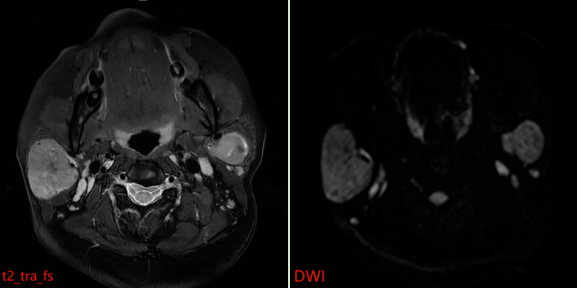

患者接受了磁共振(MR)检查,影像表现如下:

MR表现:双侧腮腺浅叶下极见结节状略混杂信号,T1以低信号为主、T2以 稍高信号为主,DWI呈稍高信号,ADC图呈稍低信号,边界清晰,增强扫描病变中等强化,强化较均匀,其内见点状无强化影。